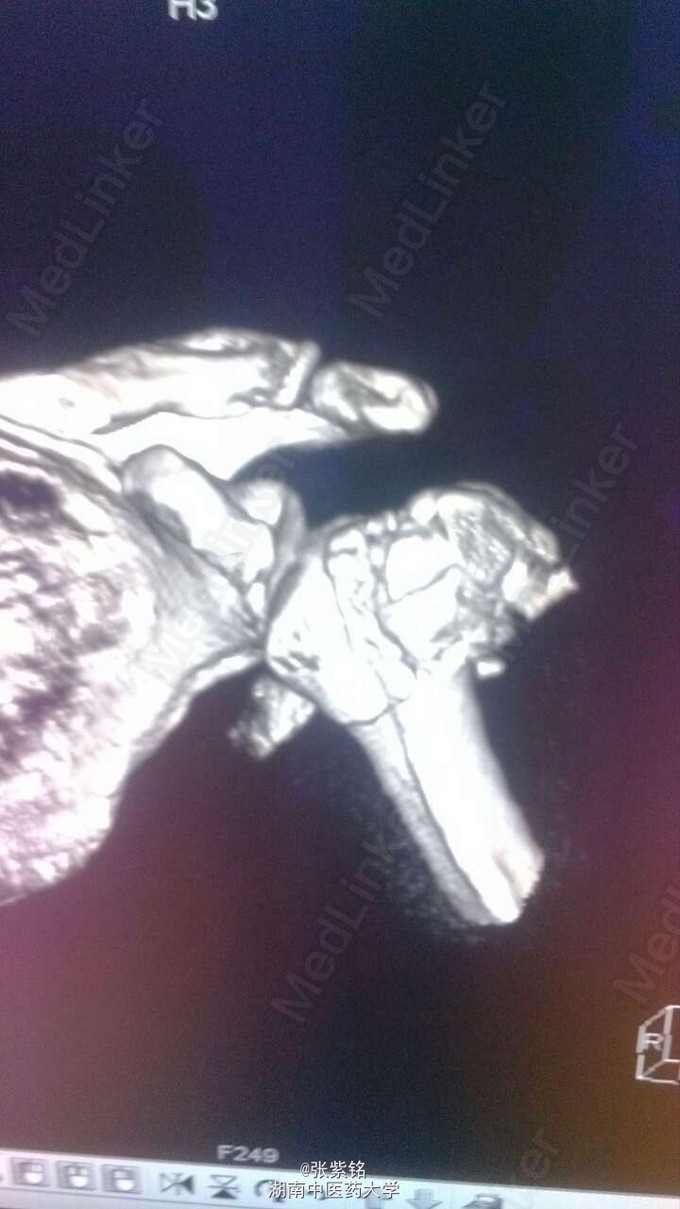

查体见:左额部可见约2cm*2cm皮下血肿,并可见一不规则伤口约2cm,伴活动性出血。脊柱驼背畸形,胸椎后凸,头部前伸体态;颈、腰部旋转活动不能,腰部于L3-5椎体棘突处压痛明显,双下肢肌力、肌张力正常。左肩部关节明显肿胀,可扪及空虚感;局部压痛明显,左Dugas征阳性,左肩关节主动上举,外展,后伸,内收活动受限;被动活动患处疼痛加剧,左侧桡动脉搏动可扪及,皮肤感觉正常,左肘、腕及各指间关节血运感觉活动正常。 X线片示:左肩关节脱位,左肱骨外科颈骨折,左肱骨大结节撕脱性骨折。